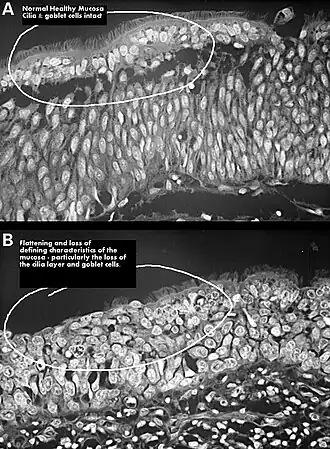

Het verlies van te veel neusschelpweefsel kan tot gevolg hebben dat het resterende slijmvlies in de nabijheid van de plaats van verwijdering en direct achter en boven dat gebied geleidelijk steeds meer ontstoken raakt, droger wordt, metaplasie en endertitis ondergaat en uiteindelijk atrofisch wordt. Als gevolg hiervan worden alle vier de functies van de neus aangetast: ademhaling, verdediging, reukzin en klankvorming. Het kan vele jaren duren voordat deze aantasting volledig tot ontwikkeling komt, hetgeen de juiste diagnose bemoeilijkt. ENS wordt soms gezien bij patiënten die relatief weinig neusschelpweefsel verloren hebben en wier neusschelpen een bijna normale omvang lijken te hebben.[10] Dit geldt in het bijzonder wanneer het voorste deel van de onderste neusschelp is weggesneden, gezien de belangrijke rol die dit deel speelt in de inwendige neusklep.[10] ENS symptomen worden door patiënten vaak snel na een conchareductie gevoeld.[10]

Er zijn er verscheidene rapportages geweest over pogingen de onderste neusschelpen te reconstrueren door implantatie van verschillende implantatiematerialen onder het slijmvlies, in een poging de normale nasale aerodynamica en fysiologie herstellen. Het aantal patiënten over wie werd gerapporteerd, was erg klein en de follow-up was relatief kort, maar de resultaten gaven enige hoop.[10][19][20] Een studie die in 2010 werd gepubliceerd, concludeerde dat operatieve verkleining van de open dwarsdoorsnede van een ‘empty nose’ om de aerodynamica positief te beïnvloeden en om de weerstand in de luchtweg te vergroten evenwel niet de luchtbewerkende functie van de neus verandert, die dus onherstelbaar beschadigd is.[9] Een andere studie rapporteerde dat, wanneer trilhaarcellen verloren zijn gegaan door degeneratie van het neusslijmvlies, zelfs operatieve sluiting van de neusgaten het aantal trilharen niet meer doet toenemen.[6]